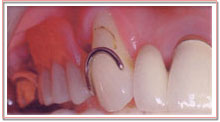

歯周病などで歯槽骨を失ってしまった場合、歯槽骨の再生治療を行います。

右の症例は一見健康そうに見えますが、歯根を支えている歯槽骨がクサビ状に溶けているための歯槽骨再生治療です。

この他にも歯抜などで失ってしまった歯槽骨の再生治療をインプラントのために行ったりします。

骨移植、骨補填財。特殊なタンパク質(エムドゲイン)、コラーゲン膜などを使用します。

| この部位の歯槽骨がなくなっています |

歯肉を切開剥離します。 |